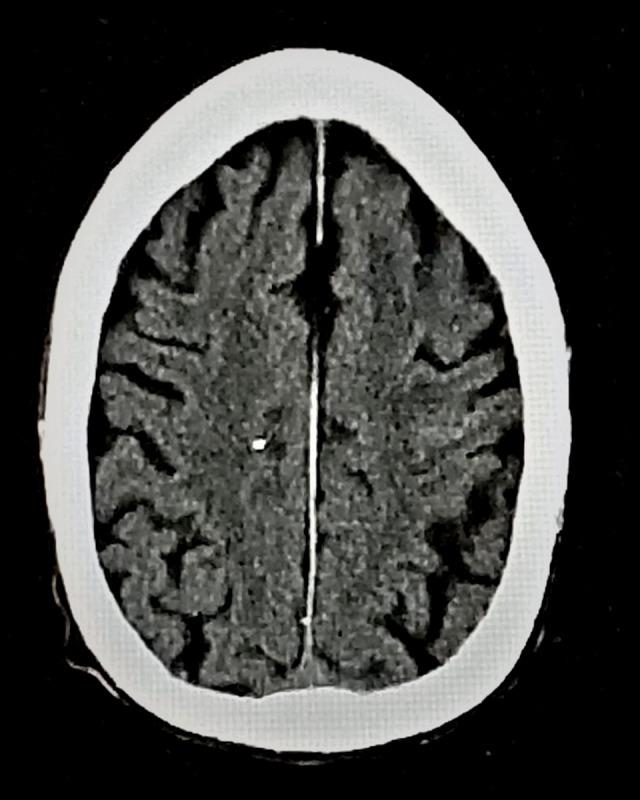

BACKGROUND Convexal subarachnoid hemorrhage (cSAH), a rare form of non-aneurysmal subarachnoid hemorrhage, is confined to cerebral convexities without extension into basal cisterns or ventricles. Typical presentation includes thunderclap/progressive headache or transient focal neurological symptoms; rare manifestations include seizures, intractable vomiting, or altered mental status. Here, we report the first case of convexal subarachnoid hemorrhage and multifocal ischemic lesions caused by infective endocarditis (IE) in a treatment-naïve advanced HIV patient. CASE REPORT A 52-year-old HAART-naïve, HIV-positive, African American man presented with altered mental status, shortness of breath, nonproductive cough, and generalized weakness. His past medical history was significant for congestive heart failure, chronic obstructive pulmonary disease, and end-stage renal disease (noncompliant with hemodialysis). Head computed tomography (CT) showed an isolated sulcal hemorrhage in the mid-left frontal lobe. Fluid-attenuated inversion recovery/gradient recalled echo sequences confirmed a hemorrhage in the left-mid-frontal sulcus, and diffusion-weighted imaging revealed multifocal bilateral ischemic lesions. Transesophageal echocardiography exhibited mitral valve vegetations. Multifocal ischemic lesions and cSAH caused by infectious endocarditis were confirmed. Initiation of intravenous vancomycin and piperacillin-tazobactam allowed the patient to have resolution of his altered mental status. A head CT 5 days later revealed the resolution of cSAH. CONCLUSIONS Infective endocarditis should be considered as an underlying etiology of cSAH, especially when present with multifocal ischemic lesions. Risk factors contributing to the development of cSAH in the IE patient population should be explored in future studies. HIV has not been previously reported in this subgroup and its prevalence should be considered. The prognosis for cSAH in relation to IE is generally favorable.

一名 52 岁的未接受抗逆转录病毒治疗(HAART)的、HIV 阳性、非裔美国男性,以意识状态改变、呼吸急促、非生产性咳嗽和全身无力为表现就诊。他的既往病史包括充血性心力衰竭、慢性阻塞性肺疾病和终末期肾病(未遵医嘱行血液透析)。头部计算机断层扫描(CT)显示左中额叶孤立性脑沟出血。液体衰减反转恢复/梯度回波序列证实左中额沟有出血,弥散加权成像显示双侧多灶性缺血性病变。经食管超声心动图显示二尖瓣有赘生物。诊断为感染性心内膜炎引起的多灶性缺血性病变和 cSAH。静脉万古霉素和哌拉西林他唑巴坦的使用使患者的意识状态改变得到改善。5 天后的头部 CT 显示 cSAH 已吸收。